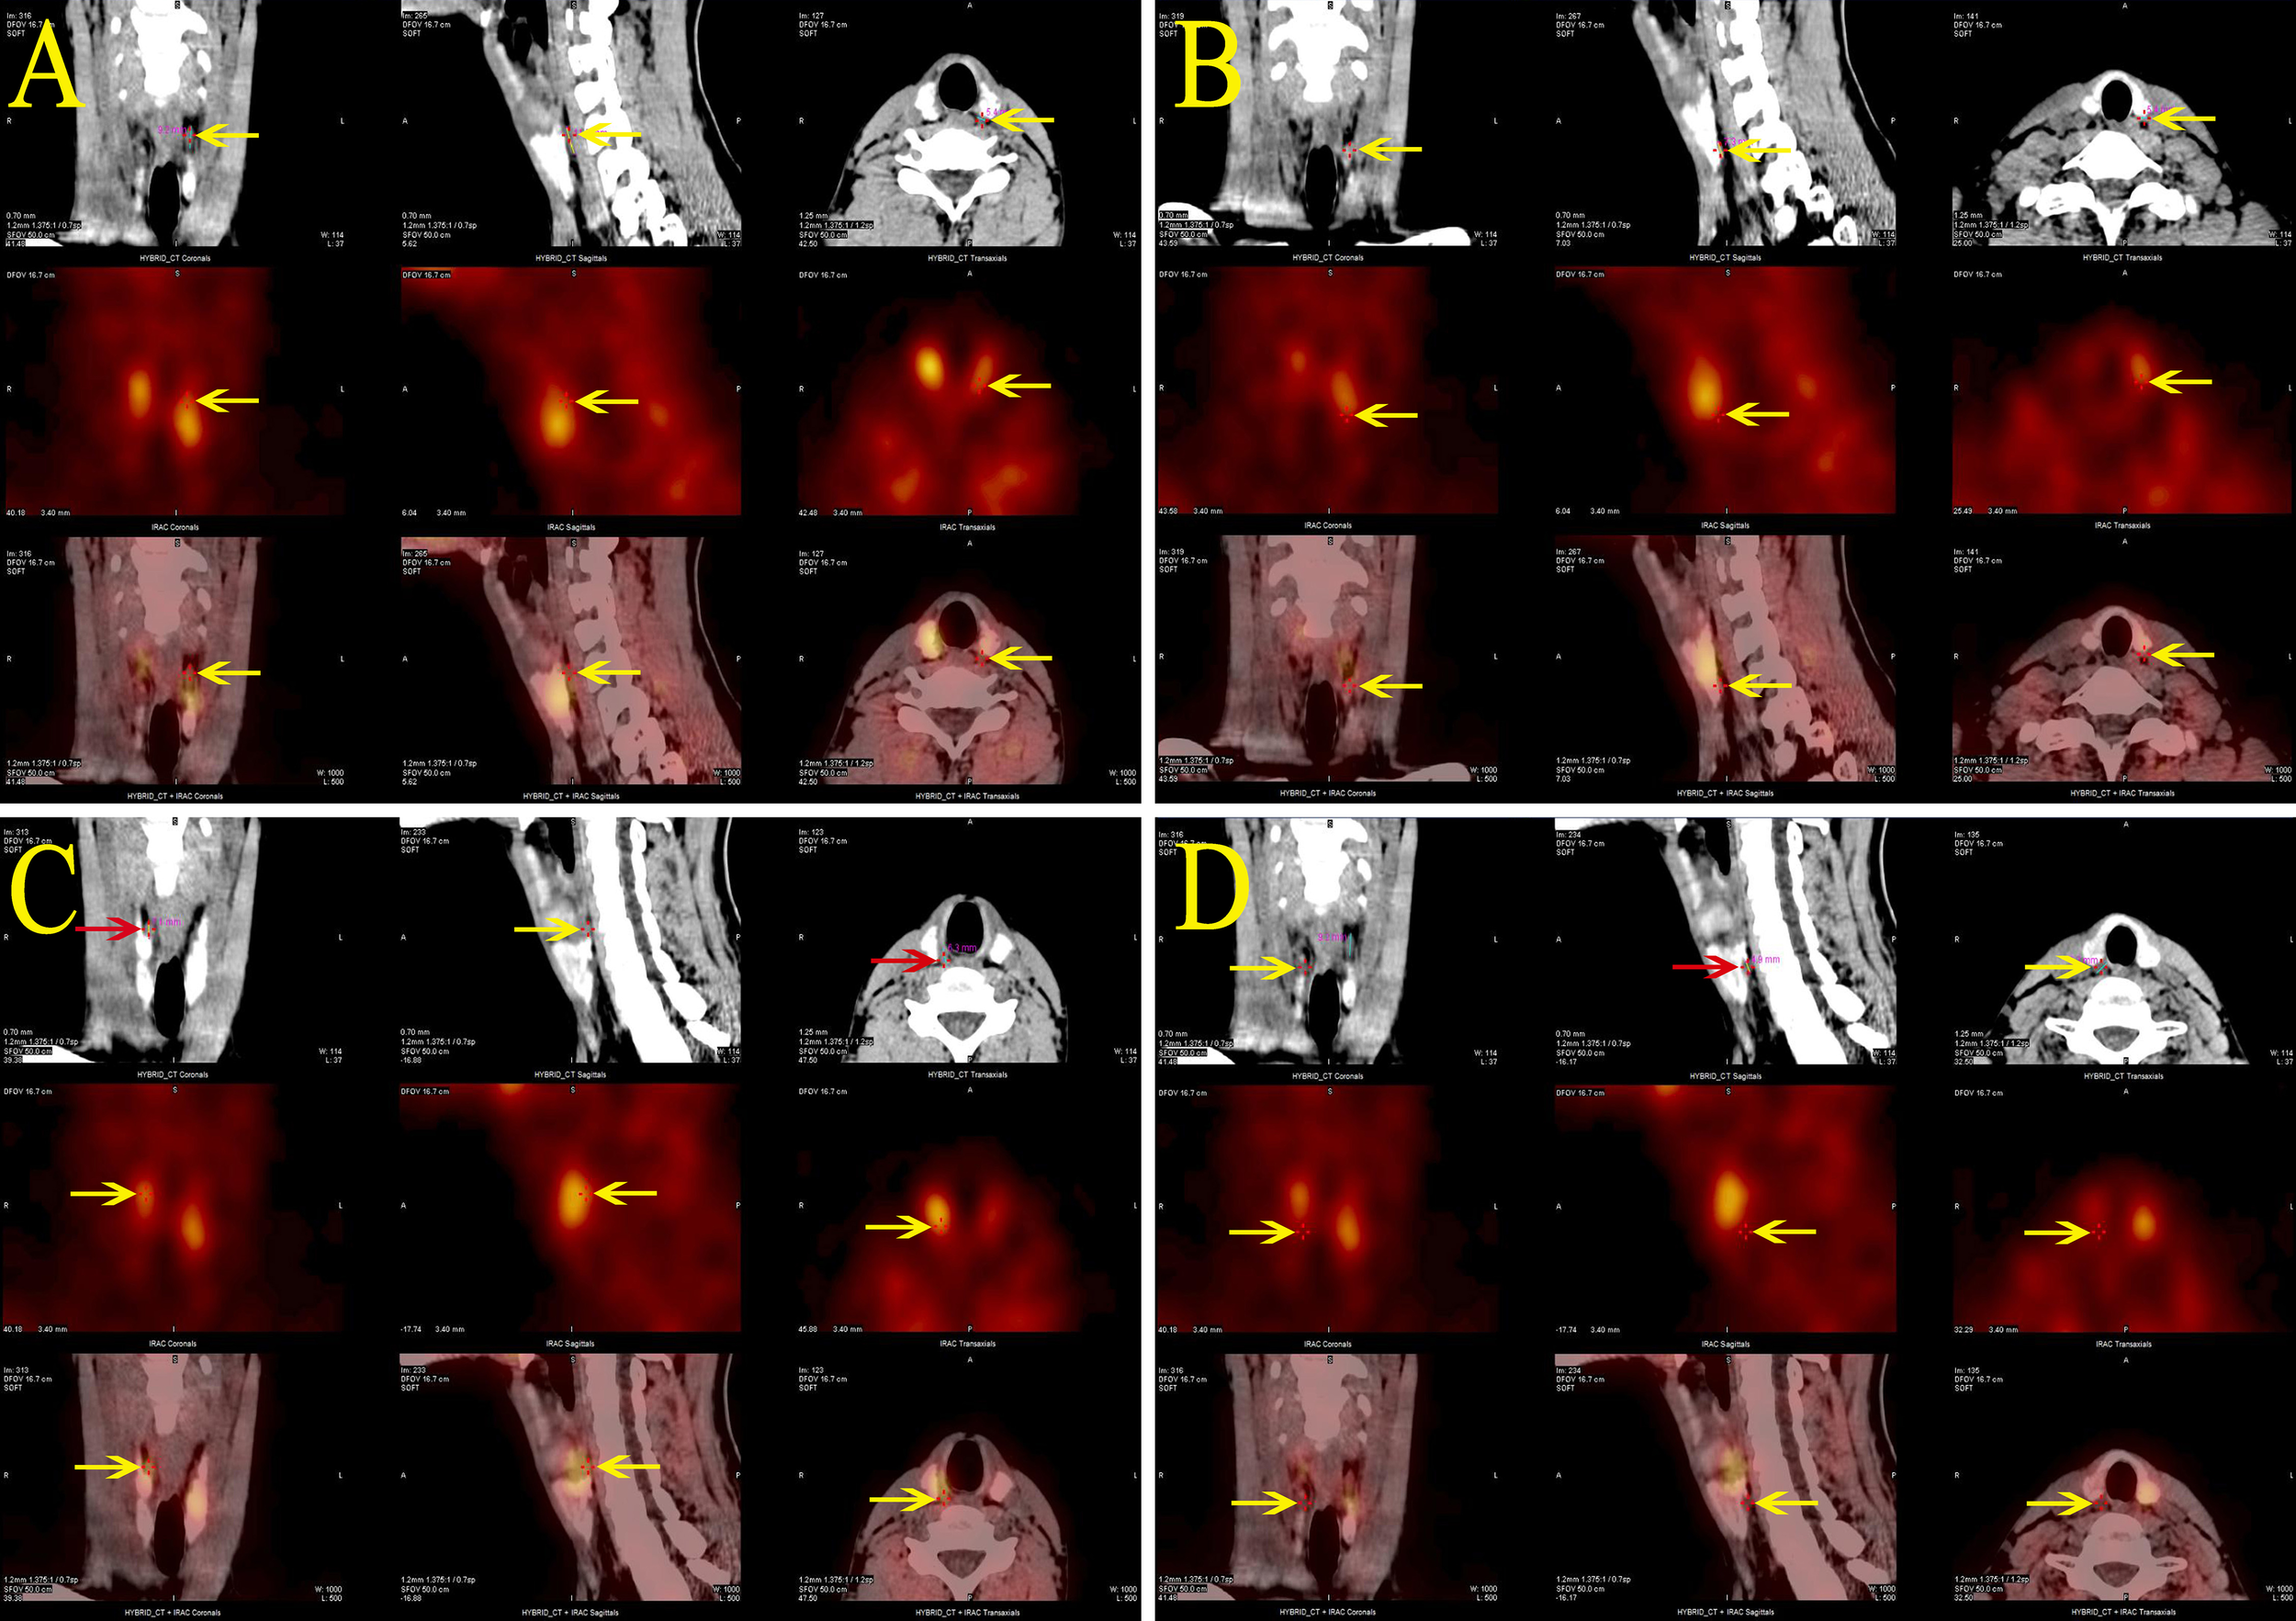

Calcium, phosphate, and PTH levels were normal during the hospital stay. But during follow-up, elevated blood calcium, PTH levels, and decreased phosphate levels were observed. Blood calcium levels were monitored at 2.62-2.81 mmol/L (normal range 2.1-2.7 mmol/L), phosphate at 1.07-1.33 mmol/L (normal range 0.81-1.45 mmol/L), and PTH at 9.85-11.35 pmol/L (normal range 1.60-6.90 pmol/L), with a 24-hour urinary calcium excretion of 12.94 mmol/24h (normal range 2.5-7.5) and urinary phosphate of 27.0 mmol/24h (normal range 22-48). Bone metabolism markers indicated a significant increase in bone turnover. The patient experienced no symptoms of polydipsia, polyuria, nausea, vomiting, abdominal pain, back pain, hematuria, or bone pain. Parathyroid ultrasound revealed: bilateral deep parathyroid solid nodules. Parathyroid single photon emission computed tomography/computed tomography (SPECT/CT) hybrid Imaging: four parathyroid glands were visualized, and there was no significant increase in parathyroid technetium-99m methoxyisobutylisonitrile (99mTc-MIBI) scan uptake (Figure 2).

Figure 2

Parathyroid SPECT/CT hybrid imaging of the proband: four areas of low-density shadows located posteriorly in the upper portions of both thyroid lobes (A, C), the posterior inferior part of the left lobe (B), and the posterior middle part of the right lobe (D), suggesting a parathyroid tissue origin. However, none of these areas demonstrated significant MIBI uptake.